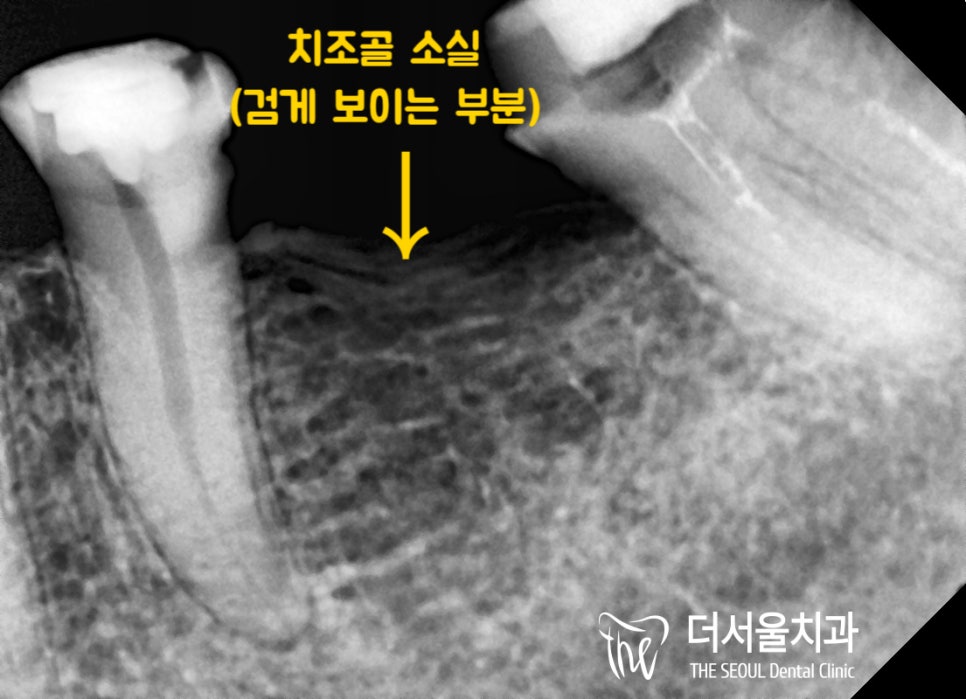

결국에는 병소가 치조골까지 퍼지게 되어

골 퇴축이 일어나게 됩니다.

파노라마로 볼 수 있듯이

염증으로 인한 골소실이 나타나 있었는데요.

실제로 기존 보철을 벗겨본 결과..

심하게 썩어있는 지대치를 확인할 수 있었습니다.